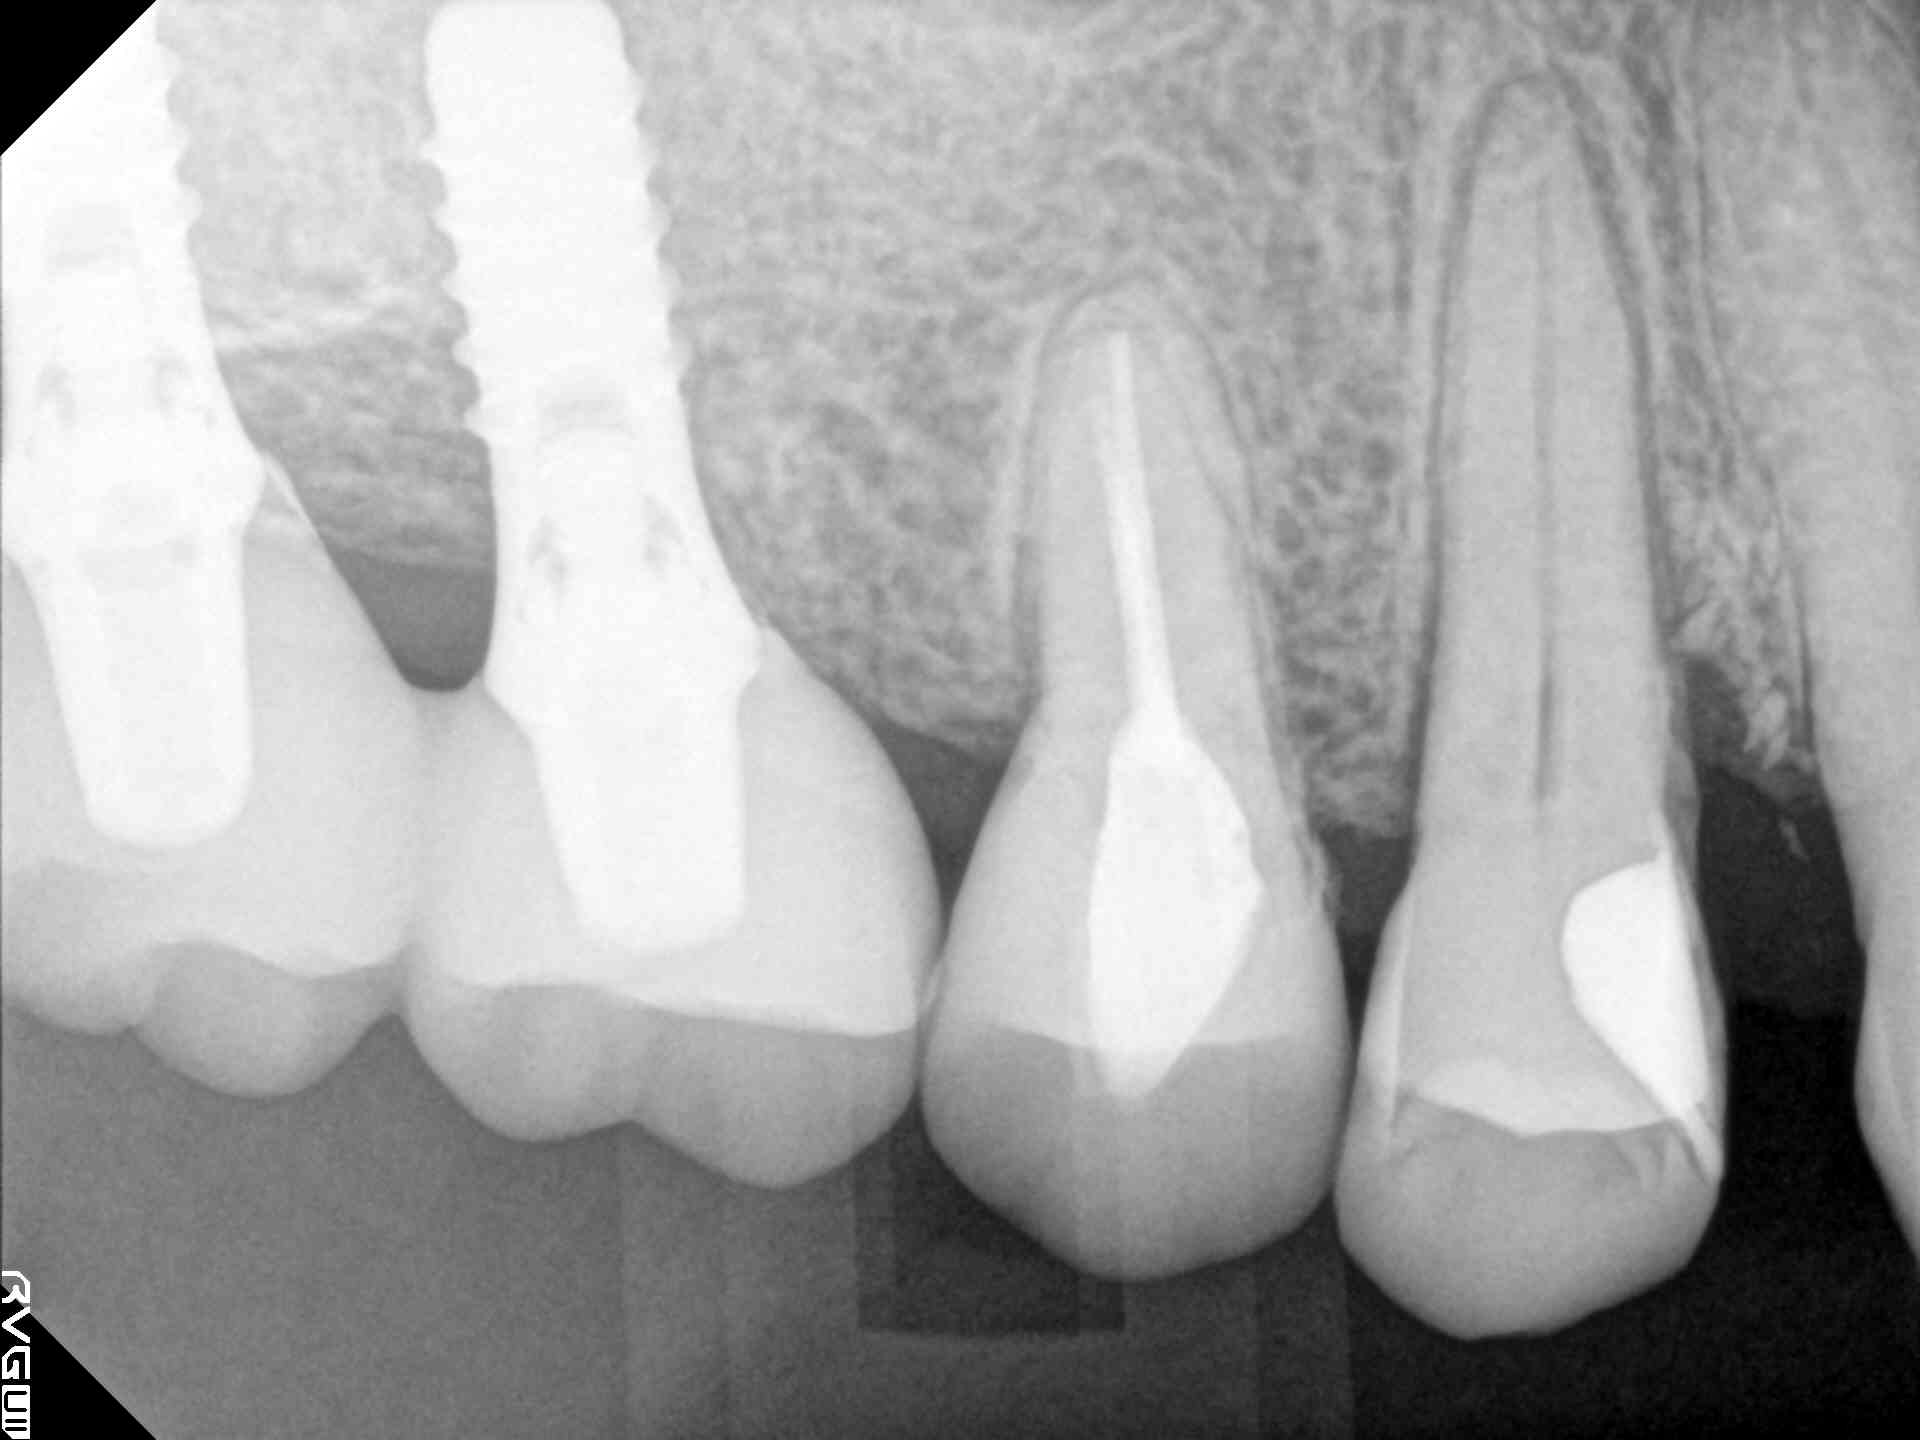

| 写真 根管1、2 |

マイクロで中を綺麗にした根管 写真 根管3、4 |